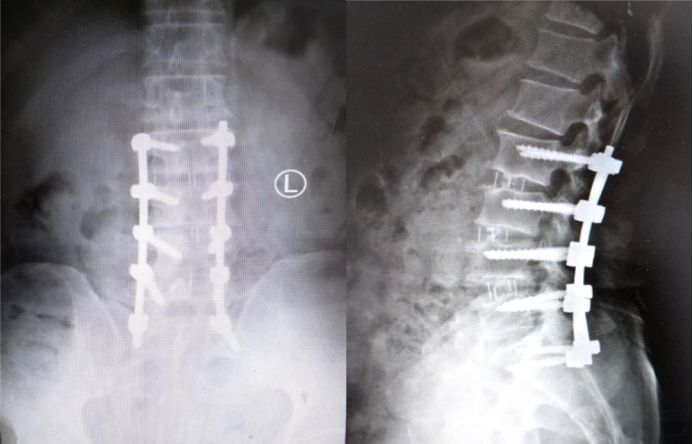

Surgical Treatment: Spinal fusion from L2 to S1, comprising lumbar laminectomy (for decompression), discectomy, interbody cage placement, and bone grafting fusion. Instrumentation involved posterior fixation using a 4.75 system with 10 screws and 2 rods, along with cage(s).

Postoperative imaging

· Implant position: No significant change compared to the immediate postoperative position.

· Dynamic Radiographs:

o Hyperextension position: 42.9°

o Hyperflexion position: 42°

o Intervertebral angle difference: 0.9°

o Intervertebral translation distance: 0 mm

· Implant Status: No deformation, migration, loosening, or fracture observed.

· CT Findings: Indicates fusion status achieved.

· Local Tissue Response: Grade 0.

· Patient Outcomes: Both the Lumbar Function Score and Quality of Life Score showed improvement compared to preoperative levels.